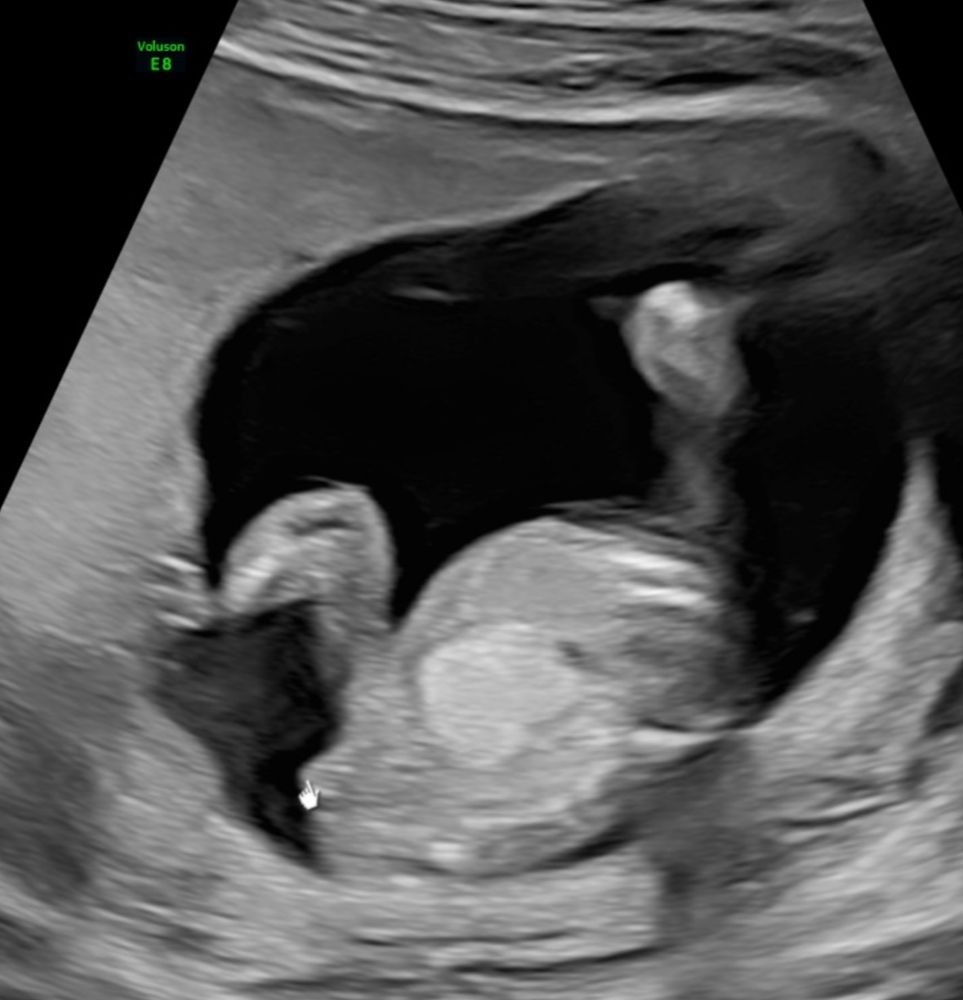

Девочки, угадываем пол 15 неделя

Пол малышаБыли на двух узи с разницей в неделю. Один врач сказал мальчик, другой - девочка

А вы что думаете?

А где мальчика то увидели? На первом девчонка вроде. А на втором я даже не разберу что. Если то что стрелочкой указано, то это пуповина, вроде бы. Но ракурс непонятный

Таня, это не ко мне вопрос где увидели. На втором фото то что стрелочкой указано это пуповина ну или нога. Она не имеет отношение к полу)) 😄

Анна, да , это у меня т9 сам дополнил. Вроде пуповина и даже переплетение видно. Рядом вроде как нога. В общем, ваш узист как художник, он так видит 😁